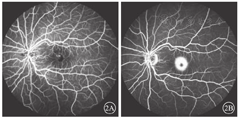

患者女,28岁。因左眼视力下降1周于2015年7月14日至淄博市中心医院眼科就诊。既往身体健康,无吸烟、饮酒史;无猫、狗等宠物接触史。自诉发病前1周出现咳嗽、流涕、发热等流行性感冒样症状;感冒症状好转后左眼出现视力下降。眼部检查:右眼视力0.3,-5.00 DS→1.0;左眼视力0.1,不能矫正。双眼眼前节检查未见明显异常。右眼视盘边界清楚,颜色淡红,血管走形正常,黄斑中心凹反光可见;左眼黄斑区约1 DD大小圆形淡黄色病灶,边界清晰,中央有不规则细点(图1)。FFA检查,左眼早期黄斑区出现不规则强荧光,周围包绕一圈弱荧光,随时间延长荧光增强;晚期黄斑区呈圆盘状强荧光,中心仍有弱荧光(图2)。OCT检查,左眼黄斑区视网膜外核层结构紊乱,外界膜及椭圆体带高低不平,嵌合体区局限性缺失(图3)。OCT血管成像(OCTA)检查,黄斑区脉络膜毛细血管扩张,局部呈强血流信号,未见明确异常血管(图4)。实验室检查,血常规、输血四项、血生化正常。TORCH检测:弓形虫IgM(-)、风疹病毒IgM(-)、巨细胞病毒IgMⅡ(-)、单纯疱疹病毒混合型IgM(-)。结核菌素试验阴性,胸部X线片检查正常。诊断:左眼急性特发性黄斑病变(AIM)。因患者处于哺乳期,未给予干预,随访观察。

首诊后1周,左眼BCVA 0.3. OCT检查,黄斑区RPE增厚,反射增强,局部椭圆体带结构不清晰(图5A)。首诊后1个月,左眼BCVA 0.8。OCT检查,黄斑区RPE增厚,呈锥状隆起(图5B)。首诊后1年,左眼BCVA 1.0. OCT检查,外层视网膜结构清晰,RPE厚度接近正常(图5C)。眼底可见黄斑病变区呈盘状色素萎缩,中央有不规则色素沉着(图6)。